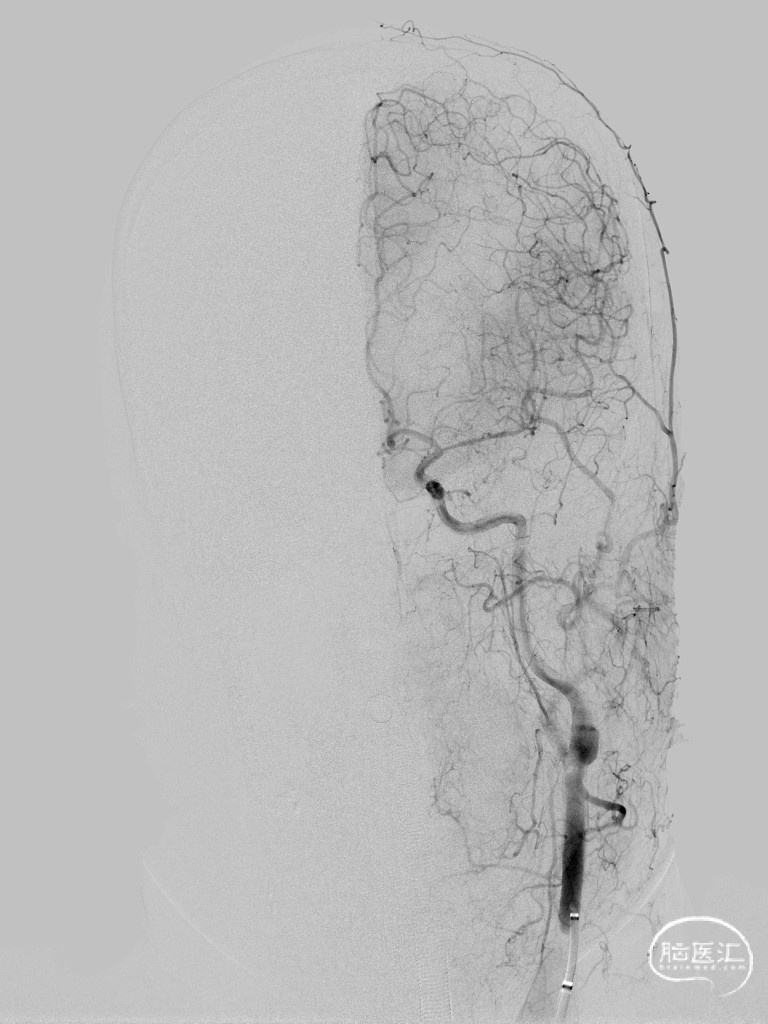

➢ 脑血管造影

➢ 术后造影